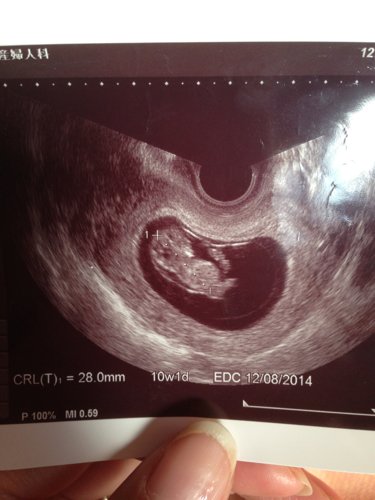

其他回答 病情分析: nt值是超声中测量妊娠10-14周胎儿颈项透明层厚度

nt值代表胎儿颈透明层厚度

nt就是颈项透明层,胎儿脖子后面的一个透明带,使用超声波查看胎儿的nt